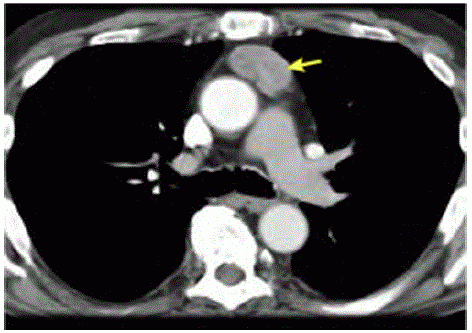

Ulna paciente de 47 anos de idade, com sint01nas gripais agudos, realizou exames de imagem de tórax por suspeita de Covid-19. A hipótese não se confirmou, porém a tomografia computadorizada de tórax, representada pela imagem a seguir, evidenciou uma massa heterogênea de contornos bem definidos em topografia de mediastino anterior, em localização de timo, de aproximadamente 4,5 cm x 2,9 cm. Não apresentava linfonodos aumentados no exame de imagem. Realizaram-se , ainda, tomografias computadorizadas de encéfalo e de abdome, que não mostraram alterações.